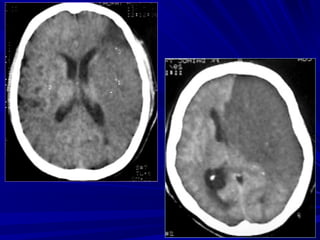

Nhồi máu não cũ

Xuất huyết sau

nhồi máu

- OÅ ñaämñoä dòch ôû vuøng toån thöông - Teo naõo ( roäng naõo thaát, raõnh naõo ) GIAI ÑOAÏN MAÕN (>8 tuaàn)